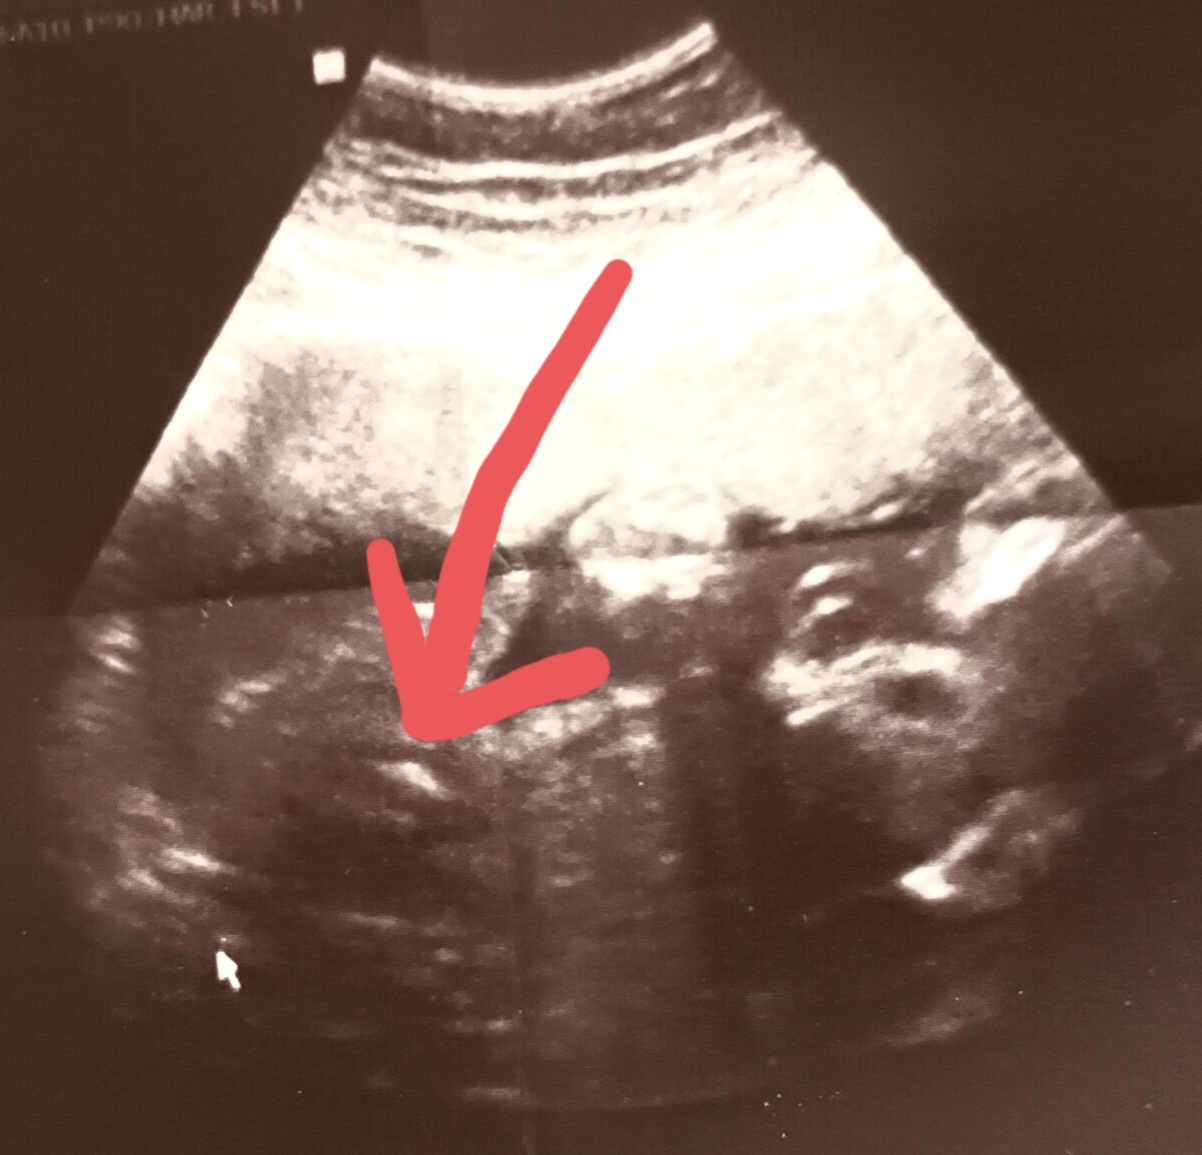

Poznáte pohlaví dítěte z této ultrazvukové fotky?